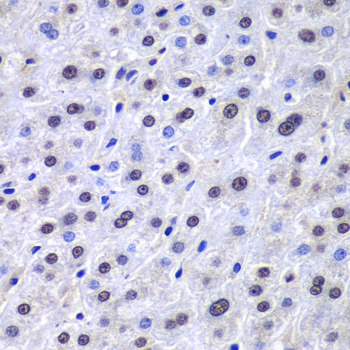

| Reactivity | Human Mouse Rat |

| Tested applications | WB IHC IF |

| Recommended Dilution | WB 1:500 - 1:2000 IHC 1:50 - 1:200 IF 1:50 - 1:200 |

Immunohistochemistry of paraffin-embedded human liver injury using APEX1 antibody at dilution of 1:100 (400x lens).